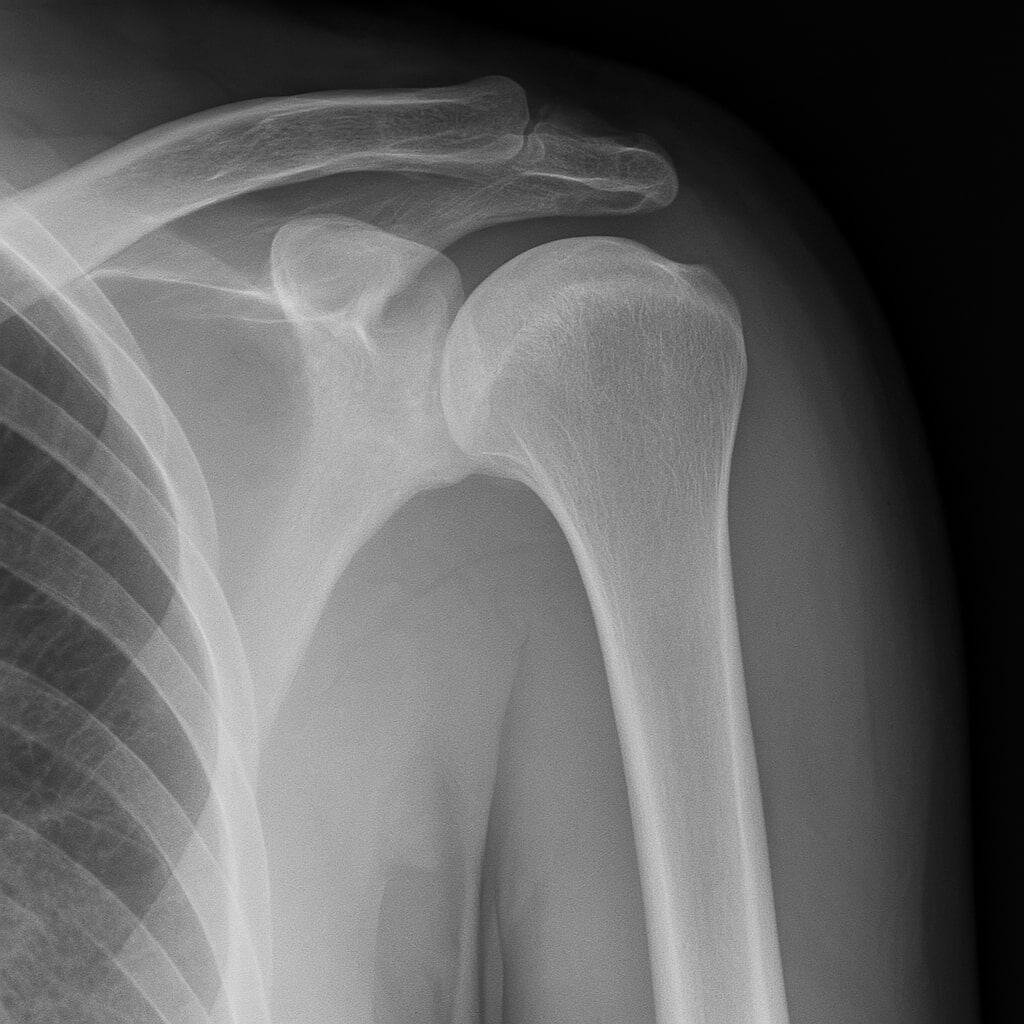

Tout d'abord, l'épaule gelée, ou capsulite rétractile, ( frozen shoulder ) est une affection musculo-squelettique. Celle-ci affecte de 2 à 5 % de la population adulte au Canada. En outre, surtout les personnes âgées de 40 à 70 ans (1). Elle se caractérise par une douleur persistante et une raideur de l'épaule. Cela limite considérablement les mouvements articulaires.

Premièrement, sur le plan de la médecine traditionnelle chinoise (MTC), l'épaule gelée est souvent interprétée comme une stagnation dans la circulation du sang et de la bioélectricité dans l'articulation de l'épaule. En particulier, le méridien du gros intestin, du poumon et de la vésicule biliaire sont souvent touchés. La douleur peut également résulter d'une accumulation de froid et d'humidité, ce qui aggrave la raideur articulaire (2).